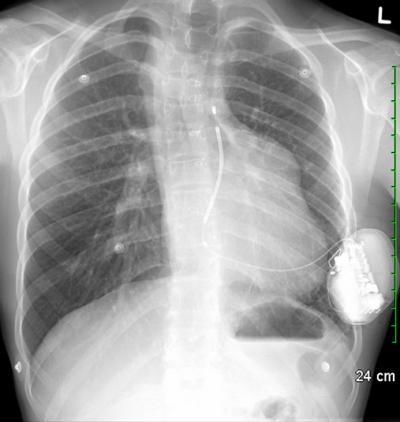

This chest X-ray shows the third subcutaneous implantable cardiac defibrillator (S-ICD) in Canada located under the skin of an 18-year-old patient with congenital heart disease. The electrode can be seen positioned near the heart, but unlike standard ICDs, no part of the device actually touches the heart.

What makes the new device special is that it is entirely subcutaneous. No part of it actually touches the heart. Instead, an electrode is implanted just under the skin near the heart. The defibrillator is connected to the electrode, and monitors the heartbeat at all times. If needed, it delivers a shock to the heart muscle to restore its normal rhythm.

Another advantage is more aesthetic in nature but, nonetheless, important for young people. A conventional transvenous defibrillator sits on the front on the chest, just under the collarbone, and is easy to see. The S-ICD, in comparison, is implanted to the side, under the patient's arm, and with a much smaller incision than with the transvenous defibrillator. That, said Dr. Nery, is an important consideration for many patients in terms of body image and quality of life.